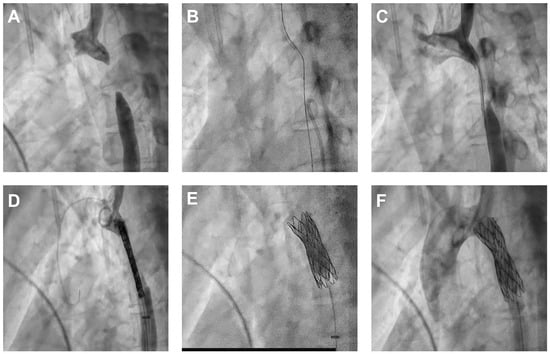

Endovascular Repair of Thoracic Aortic Atresia in Adults: A Narrative Review of a Rare Entity and Emerging Technique

Thoracic aortic atresia in adults represents a rare and extreme manifestation of aortic coarctation, marked by complete luminal occlusion and frequently compensated by extensive collateral circulation. This narrative review critically evaluates existing literature and institutional experience concerning surgical and endovascular repair strategies for [...] Read more.

Thoracic aortic atresia in adults represents a rare and extreme manifestation of aortic coarctation, marked by complete luminal occlusion and frequently compensated by extensive collateral circulation. This narrative review critically evaluates existing literature and institutional experience concerning surgical and endovascular repair strategies for aortic atresia, synthesizing evidence from related aortic arch pathologies due to the absence of direct comparative studies. Both treatment modalities—open surgical repair and catheter-based recanalization with stenting—have evolved significantly, presenting distinct advantages and limitations influenced by patient anatomy, age, and comorbidities. While surgical repair remains the standard for neonates, infants, and complex cases due to superior long-term durability and blood pressure control, endovascular procedures using chronic total occlusion technique and covered stents offer less invasive alternatives with rapid recovery, particularly in adults with suitable anatomic characteristics. The review highlights procedural considerations, including technical approaches, stent selection, and potential complications such as restenosis, hypertension, and vascular injury. Individualized, multidisciplinary decision-making remains essential, with shared consensus guiding therapy in the absence of randomized trials. The article identifies critical gaps in knowledge, emphasizing the need for multicenter, long-term studies and technological advances—including hybrid and personalized strategies for optimal management and for improving outcomes in this challenging congenital condition. Full article

Show Figures

Figure 1